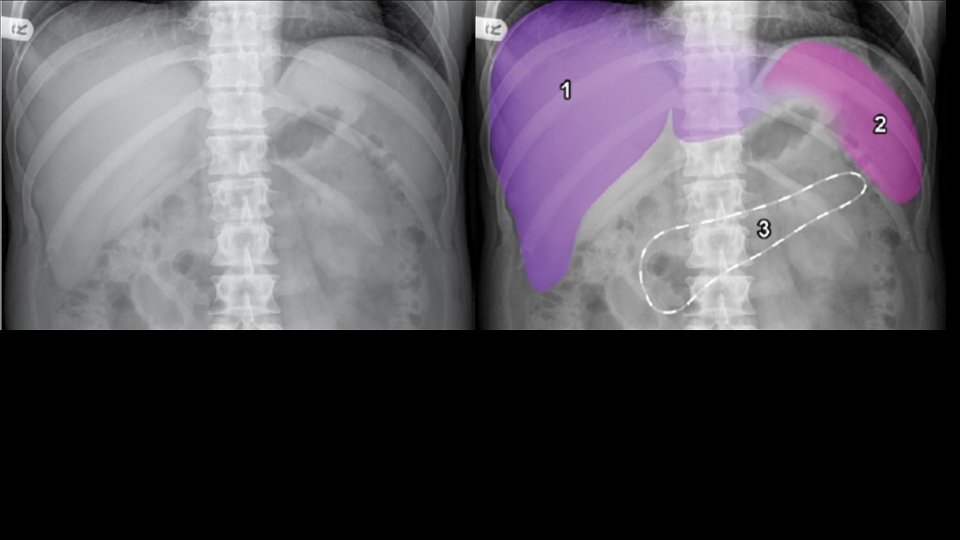

Abdominal viscera • Solid • • Liver Spleen Kidneys and adrenals Pancreas • Hollow • Stomach • Small bowel • Large bowel • Musculoskeletal parts

Normal Anatomy